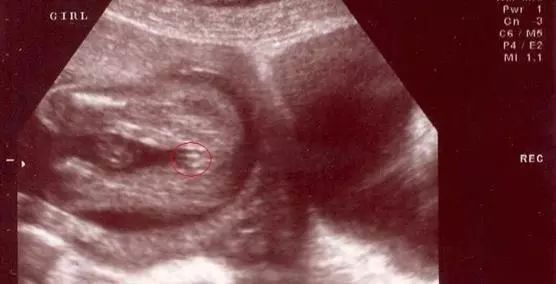

女宝宝的b超图

三条白线是明显的女宝特征,如果没有看到明显的三条白线,就看两腿之间有没有突出的东东,且中间有小凹槽的,就是女宝。